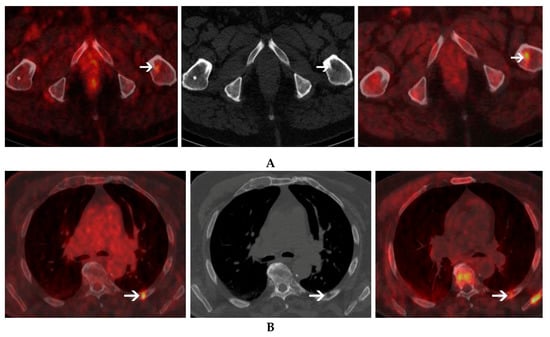

- Cassou-Mounat, T.; Balogova, S.; Nataf, V.; Calzada, M.; Huchet, V.; Kerrou, K.; Devaux, J.Y.; Mohty, M.; Talbot, J.N.; Garderet, L. 18F-fluorocholine versus 18F-fluorodeoxyglucose for PET/CT imaging in patients with suspected relapsing or progressive multiple myeloma: A pilot study. Eur. J. Nucl. Med. Mol. Imaging 2016, 43, 1995–2004. [Google Scholar] [CrossRef]

| Cassou-Mounat et al. (2016) [26] | 21 | Retrospective | Relapse or Progression | 18F-Choline 18F-FDG | 3 MBq/kg | 10–20 min. | None | 121 (65/56) | 69 (65/4) | 3 (3/3) | 3 (3/3) | 3.8-5.7 (1.6–16) | 3-4.5 (1.6–20.6) |